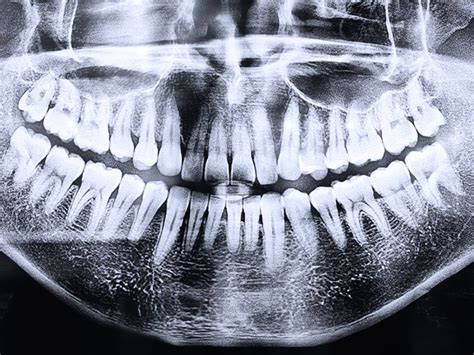

La radiografía panorámica dental, también conocida como ortopantomografía, ofrece una imagen general de la boca, mostrando los maxilares, la mandíbula y los dientes en una sola película. Sin duda la ortopantomografía es el método preferido de los dentistas.

Esta radiografía se realiza a través de una máquina de rayos X que rodea la cabeza del paciente con dos pantallas receptoras de la imagen. Es diferente a otras radiografías, ya que utiliza menos radiación, se realiza en pocos segundos y se hace en una sola toma. Para una buena toma, es importante la correcta colocación del paciente en el escáner, debido a su sensibilidad y la precisión de los resultados; cualquier error puede modificar el resultado.

La ortopantomografía tiene la desventaja, en relación con el Tac 3d, de que es una radiografía de dos dimensiones, todo lo vemos aplanado. Vemos a lo alto y a lo ancho pero no el grosor.